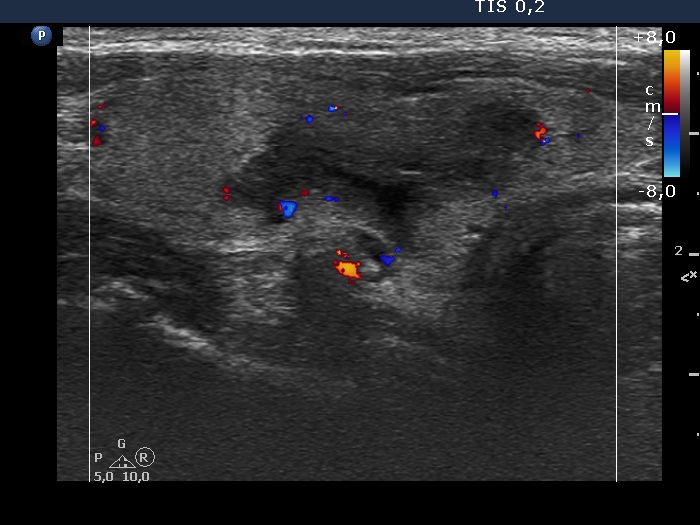

The borders of the nodule - case 1275 (ultrasonographic picture 8)

Right lobe, longitudinal scan, color Doppler mode - after the removal of 14 mL brown cystic fluid. The vascularization is not specific.